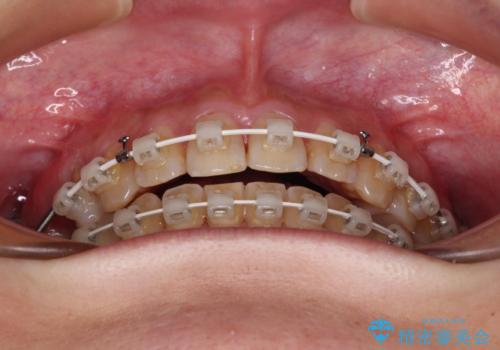

- 奥歯に問題が多くて困っているとのことで来院された患者様です。

開咬により奥歯のみが接触している状態で、前歯部にほとんど接触のない状態で、奥歯に非常に負担のかかる咬み合わせでした。

また、欠損や根管治療の必要な歯など、むし歯による問題も多く散見されました。

まずはむし歯の治療を行い、その後ワイヤー矯正にて咬み合わせを改善し、途中インプラント埋入を行い、矯正治療後に補綴治療を行うこととしました。